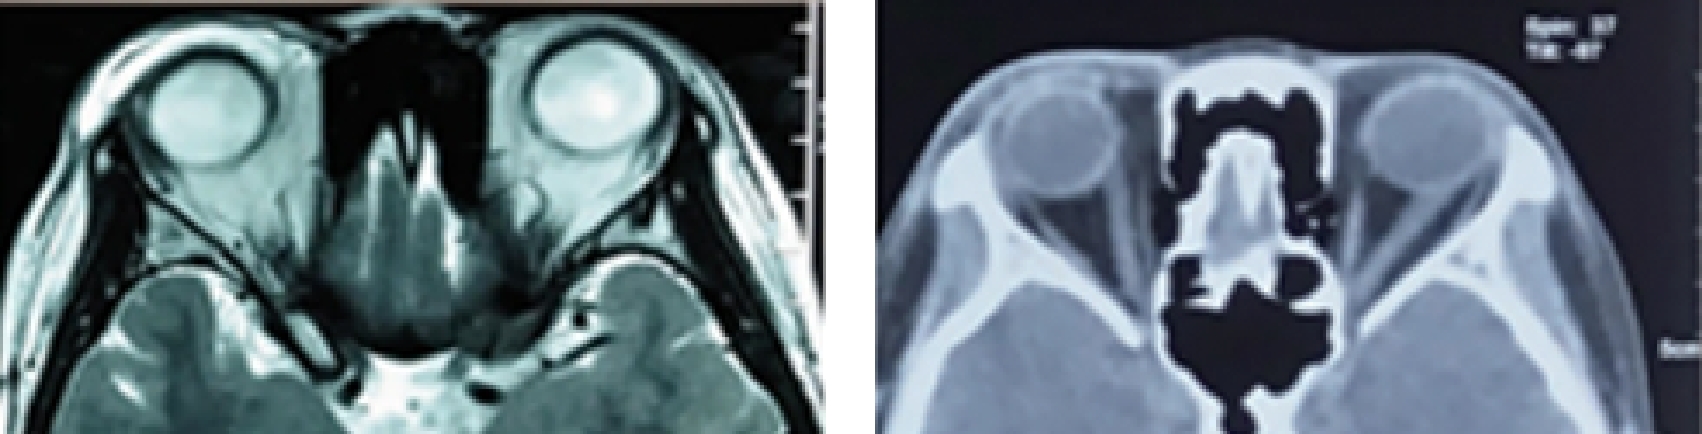

• 博来霉素多点注射联合介入栓塞治疗眼眶血管畸形的临床研究

2025, 35(17):61-66. DOI: 10.3969/j.issn.1005-8982.2025.17.010

摘要 (162) HTML (42) PDF 912.73 K (88) 评论 (0) 收藏

摘要:目的 评估博来霉素多点注射联合介入栓塞治疗在治疗眼眶血管畸形中的临床疗效及安全性。方法 选取2020年1月—2023年12月在中国人民解放军陆军第七十三集团军医院接受治疗的115例眼眶血管畸形患者为研究对象。随机分为两组,对照组(57例)接受经导管动脉硬化栓塞治疗,治疗组(58例)接受博来霉素多点注射联合经导管动脉硬化栓塞治疗。采用数字减影血管造影指导介入治疗,并通过临床症状改善情况、瘤体面积变化、瘤体厚度变化、影像学评估及不良反应发生率等评价治疗效果。结果 治疗组的总有效率达到100%,高于对照组的85.96%(P <0.05)。治疗组治疗前后瘤体面积与瘤体厚度的差值均大于对照组(P <0.05)。影像学评估显示,治疗后眼眶血管畸形显著缩小,周围肿胀组织逐步恢复至正常状态。治疗组和对照组的不良反应发生率分别为3.44%和8.77%,差异无统计学意义(P >0.05)。两组均无严重并发症报告。结论 博来霉素多点注射联合经导管动脉硬化栓塞治疗在改善眼眶血管畸形临床症状和减小瘤体尺寸方面表现出显著优势,并且不良反应发生率较低,是一种有效且安全的治疗策略。